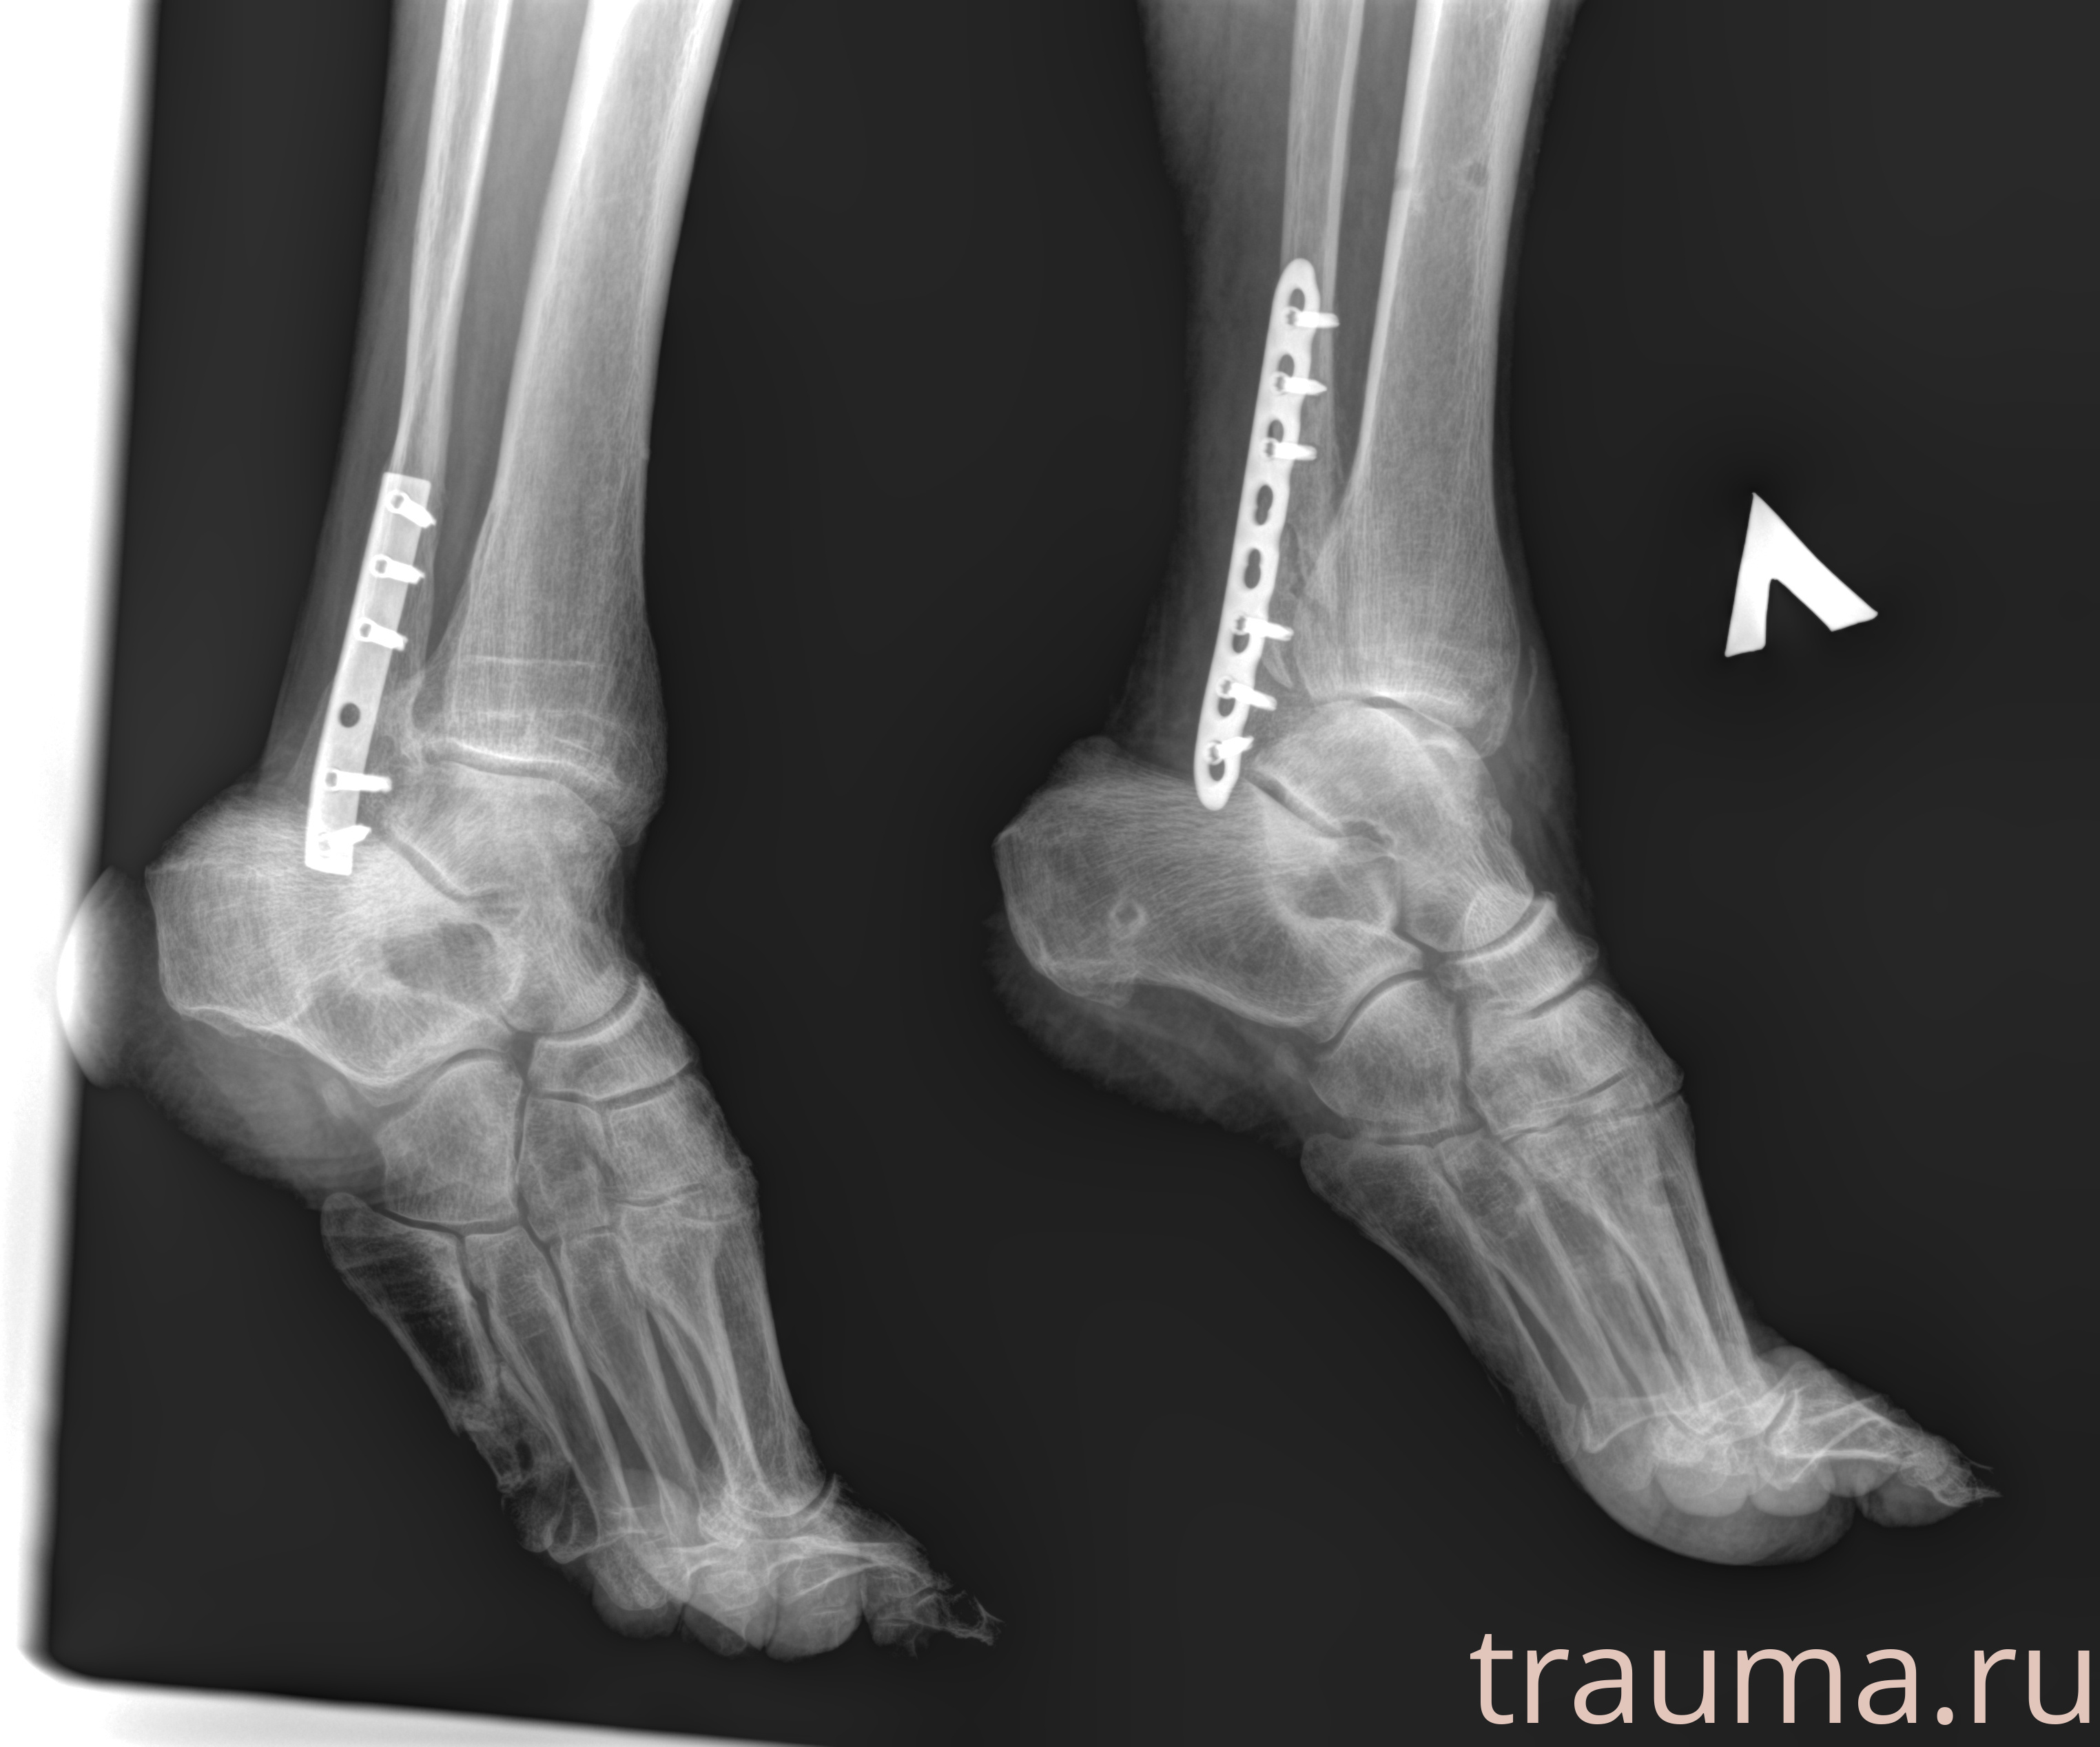

Рентгенограммы